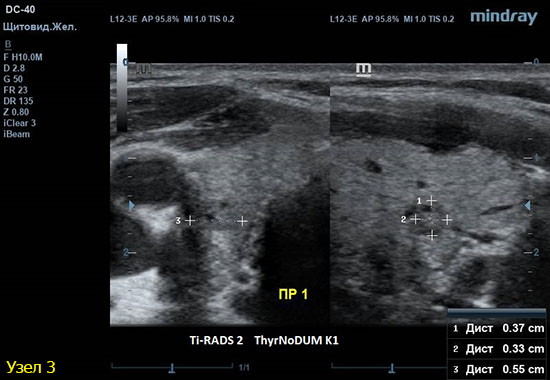

3) Узел правой доли, не прорастает капсулу щитовидной железы (0 баллов), больше широкий чем высокий (0 баллов), не имеет кальцинатов (0 баллов), с ровным четким контуром (0 баллов), изоэхогенный (1 балл), смешанной структуры (1 балл). Количество баллов 2, ACRTi-RADS2, ThyrNoDUMК1. Пункция не показана в связи с низким риском.